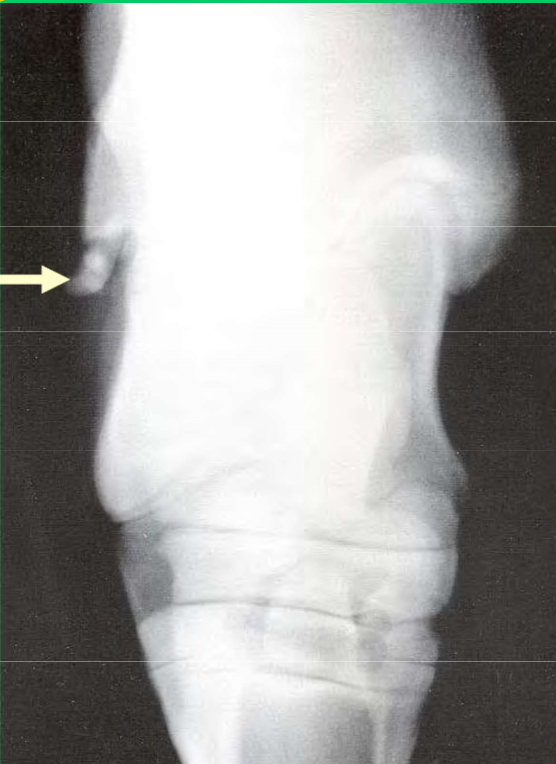

What position was used to take this radiograph

DLPM O

Dorso-Lateral Proximal Medial Oblique